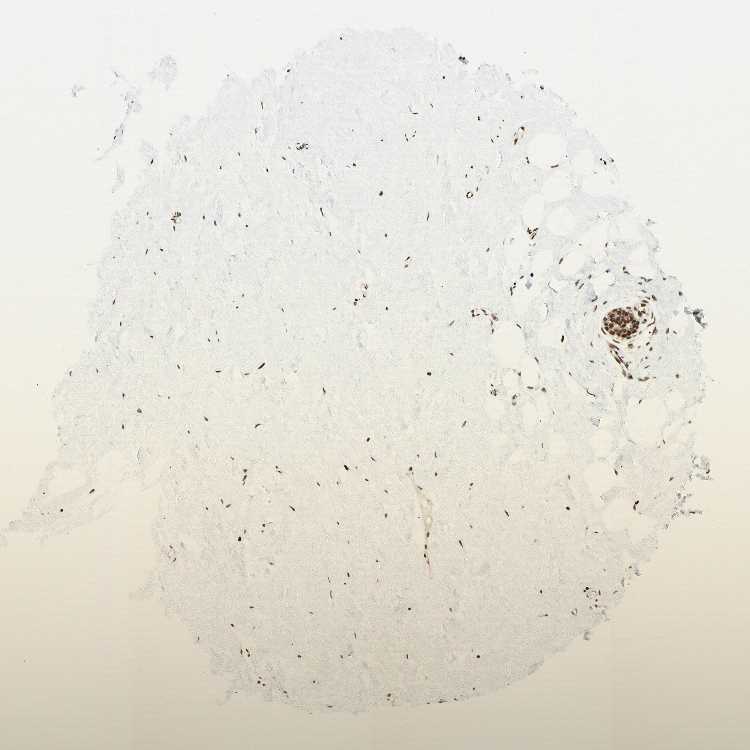

BREAST - Antibody stainingi

Antibody staining in the annotated cell types in the current human tissue is reported as not detected, low, medium, or high, based on conventional immunohistochemistry profiling in selected tissues. This score is based on the combination of the staining intensity and fraction of stained cells.

Each image is clickable and will lead to virtual microscopy that enables deeper exploration of all samples and also displays staining intensity scores, fraction scores and subcellular localization as well as patient and tissue information for each sample.

Antibody HPA007644Antibody CAB004435Antibody CAB016225

Adipocytes MediumHighHigh

Glandular cells HighHighHigh

Myoepithelial cells HighHighHigh